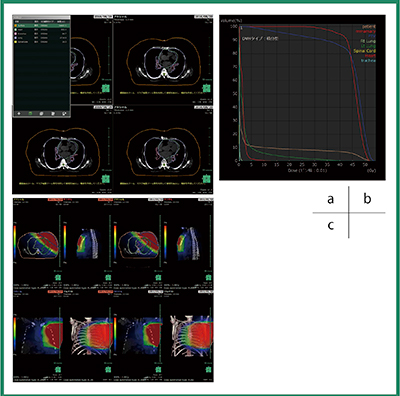

RTアシスト(CT,RT,PT,MRI用解析アプリケーション)(W.I.P.)

さまざまな施設で,汎用・解析アプリケーション(頭頸部,胸部,循環器,消化器領域など)に搭載されている臓器抽出機能を利用し,術前シミュレーション用画像の作成が行われている。VINCENT Ver.5では,この長年培ってきた臓器抽出機能を,放射線治療計画情報の作成に必要なリスク臓器(Organ At Risk:OAR)の輪郭作成へ応用した“RTアシスト”を開発した。

頭頸部,胸部領域の治療計画を作成する時に必要なOARを,VINCENTのプリセット機能から1クリックで作成できる。また,放射線治療後の外科的手術時に術前カンファレンス,患者へのインフォームドコンセント目的で線量分布図の観察,Dose Volume Histogram(DVH)の作成機能も搭載している(図4)。

図4 RTアシストの画面例

a:VINCENTのプリセット機能を利用して1クリックで体表,心臓,気管支(気道),肺,脊髄のマスク領域を自動抽出後,OARを作成した例。作成したOARはRT-Structure Setとして放射線治療計画システムへストレージする。

b:線量分布図の一覧表示例。複数照射したおのおのの線量分布図を院内のVINCENTクライアントで閲覧できる。また,異なる照射日時の検査を剛体,非剛体位置合わせした積算線量分布図の閲覧も可能である。

c:DVH例。OAR(RT-Structure Set),線量分布図(RT-Dose)からDVHを作成し,院内カンファレンスなどでOAR,GTVなどに投与された積算線量などを相対値として表示する。